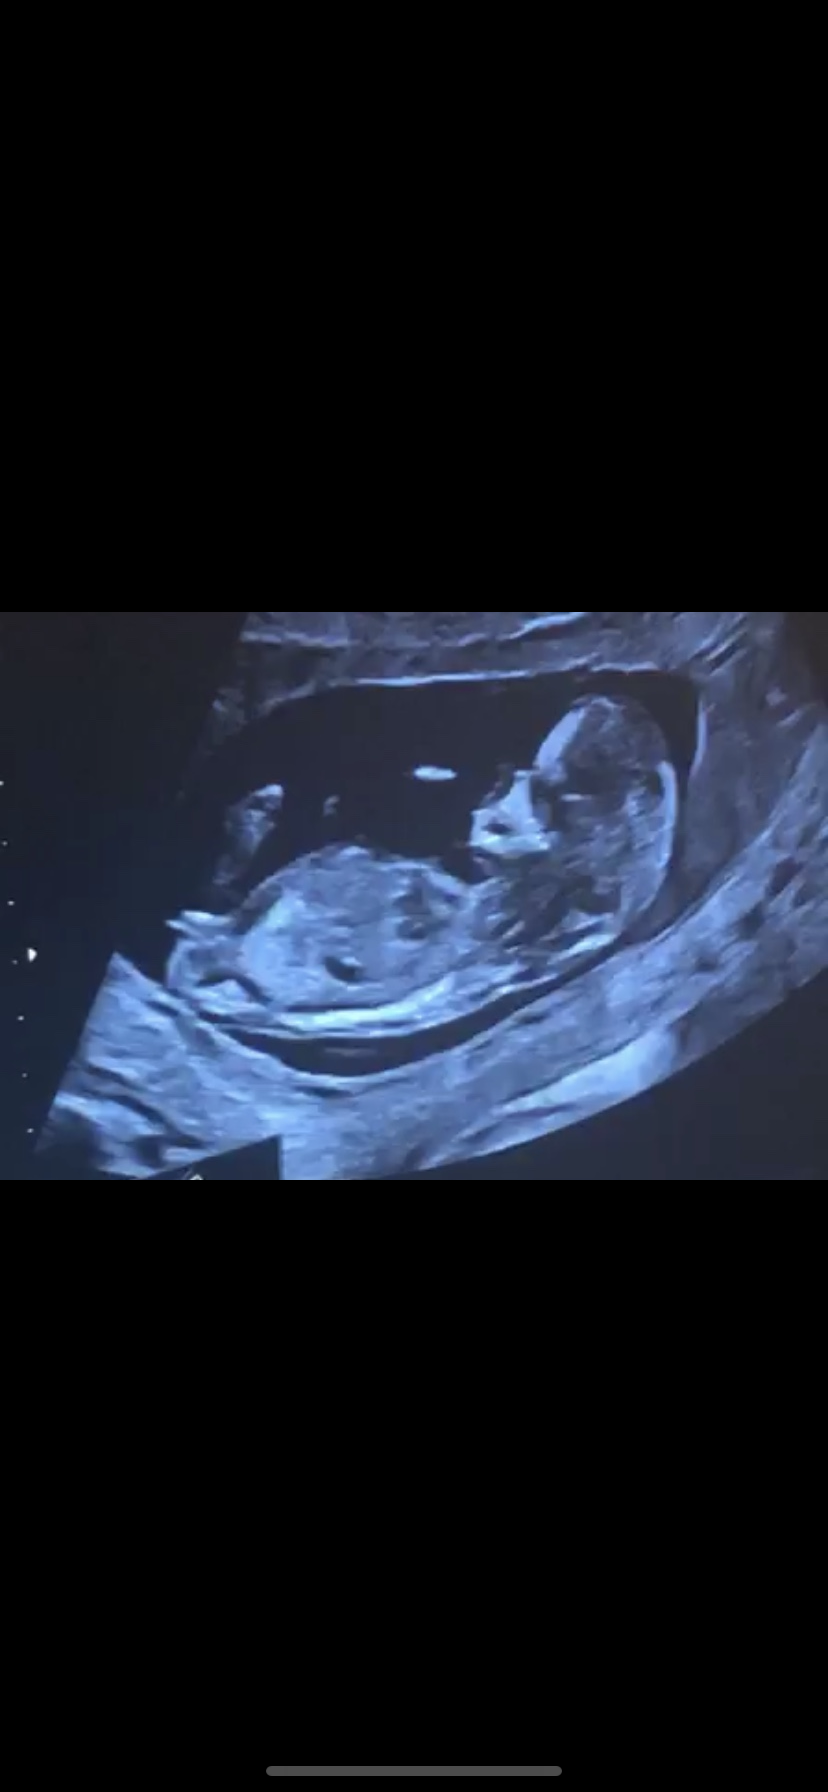

الي فهمته من هالنظريه يشوفون اخر جزء للطفل ف الاسابيع ( 10 -13 ) اذا كان مرتفع لاعلى فهو ذكر اما اذا موازي للعمود الفقري فهي انثى

من تعرف هالصوره ف الاسبوع 13 🌹